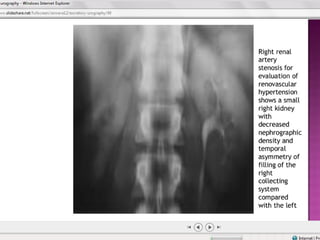

GU Tb-plain KUB

Disparity in renal size on plain films may indicate

early increase in size of the affected kidney due to

caseous lesions or a shrunken fibrotic kidney of

autonephrectomy.

Calcifications are seen in 30% to 50%

A characteristic diffuse, uniform,extensive

parenchymal, putty-like calcification, forming a lobar

cast of the kidney is seen with autonephrectomy